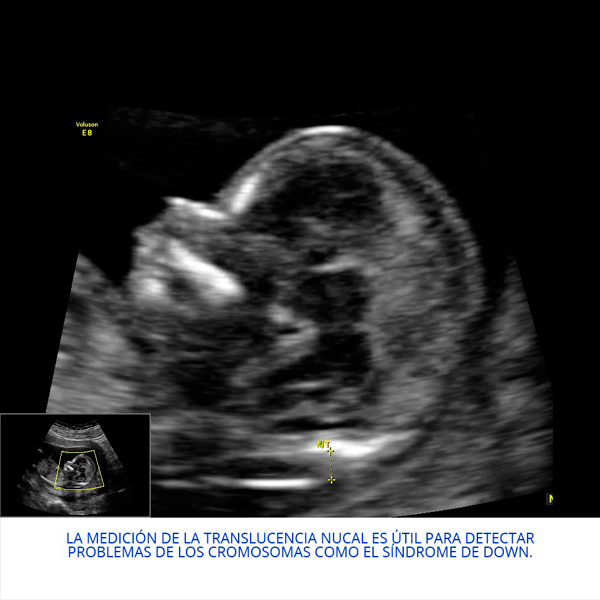

Actualmente realiza un Doctorado Internacional en Medicina Fetal avalado por las universidades de KU Leuven (Bélgica), Universidad de Barcelona (España) y la Universidad de Lund en Suecia, tres instituciones líder en el segmento de la medicina fetal a nivel mundial.